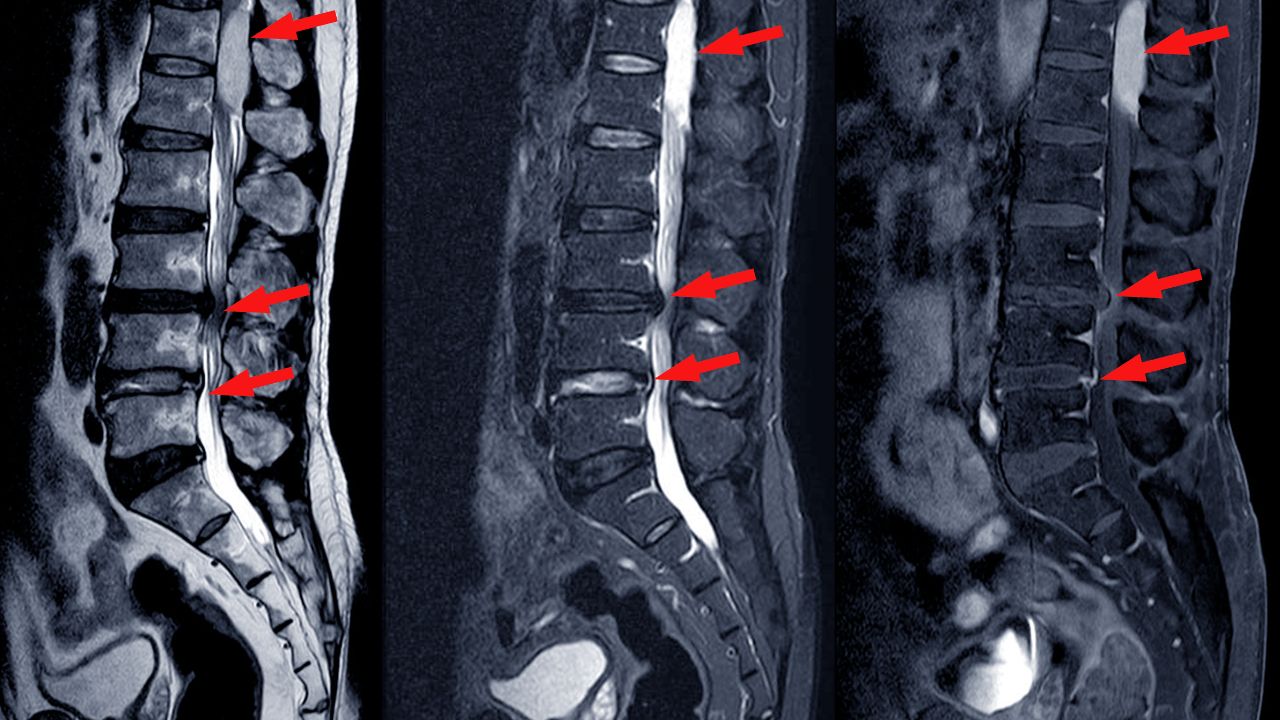

تشخیص تنگی کانال نخاع

تشخیص با بررسی دقیق علائم، معاینه فیزیکی و تصویربرداری انجام می‌شود.

پزشک با مشاهده نحوه ایستادن، راه‌رفتن، خم‌شدن و ارزیابی واکنش‌های عصبی مانند رفلکس‌ها، قدرت عضلات و حس لمس در اندام‌ها، محل و شدت فشار روی عصب‌ها را بررسی می‌کند. برای تأیید تشخیص، معمولاً از تصویربرداری‌های زیر استفاده می‌شود:

• رادیوگرافی (X-ray) برای مشاهده تغییرات استخوانی مثل خارهای استخوانی و کاهش فضای دیسک‌ها

• MRI برای دید دقیق‌تر از نخاع، ریشه‌های عصبی و دیسک‌ها

• سی ‌تی اسکن و در صورت نیاز میلوگرام